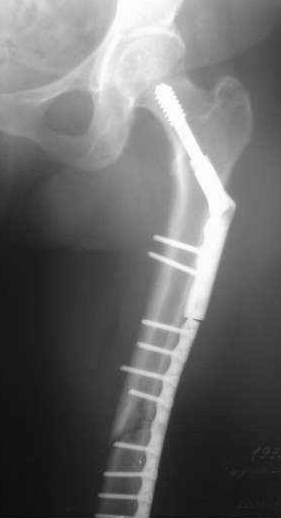

Сегодня мною была осмотрена больная, которой я выполнил накостный остеосинтез около четырех месяцев назад по поводу фрагментарного перелома бедра на уровне средней трети и межвертельной зоны.

Перелом синтезированный DHS сросся, а вот на уровне средней трети - нет. И, похоже, есть нехорошая тенденция к резорбции.

Больную беспокоит умеренный отек голени и стопы. Нагрузку на конечность не разрешаю, ибо недавно у молодого пациента при аналогичном переломе и остеосинтезе произошел перелом пластины на уровне нижней трети бедра...

Обращаясь к Александру Николаевичу, хочется узнать о целесообразности удаления металлоконструкции и интрамедуллярном штифтовании у них в институте у данной больной. Если есть резон, то нужно обговорить финансовую сторону вопроса ...

По поводу моей больной с фрагментарным переломом бедра ...

Больная 47 лет, поступила в отделение после автодорожной травмы от 08 июля сего года с DS: ЗЧМТ, СГМ. Закр. чрезвертельный перелом и перелом с/3 левого бедра со смещением. Ушиб и рваная рана левого коленного сустава. Соп.: Хр. железодефицитная анемия. (Гемоглобин при поступлении 71 г/л). 08 июля - ПХО ран колена.

11 июля остеосинтез бедра DHS + LC DCP.

Социальный статус ... пенсионер, не работает (вернее работает с детьми, частные предприниматели).

Я выкладывал на Форум этот случай, где высказывались опасения, что не исключается варусная дислокация межвертельного перелома на фиксаторе из-за малой длины Screw ... вроде пронесло ... перелом сросся. Но маленькая

победа в отдельной битве, все же не принесла победы в целом... Остается неопорная конечность, ограничение движений в коленном суставе 180 - 150 град., отечность голени и стопы, по-видимому, из-за сосудистой недостаточности, гипотрофии

мышц ноги ... При выписке из стационара Hb - 97 г/л (препараты железа, рибофлавины).

По настоящий момент наблюдается амбулаторно. Передвигается с опорой на костыли. Горит желанием встать "на крыло" ... Ждем Вашего решения. Может быть нужны дополнительные снимки?

Возьметесь ли за этот случай? Ну, и самое главное - стоимость лечения ...